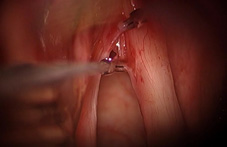

手術加上麻醉的時間,全程約一個小時左右。手術後噤聲期為7天,一個月的恢復期內也需避免胃食道逆流之刺激,以免對剛手術完的聲帶造成傷害。少部分患者術後可能因皮瓣癒合不佳,出現纖維化或有斑痕組織(約5%),可於聲帶局部施打類固醇以改善症狀。除了上述常見病變外,顯微皮瓣手術亦可應用在較特殊的案例,如聲帶沾黏或咽喉狹窄等(如:圖三、圖四),克服傳統手術容易復發再次沾黏的困境。不論是哪一種手術技法,手術後都建議患者配合嗓音治療,可以加速嗓音的恢復並減少日後復發的機會。

圖四、以顯微皮瓣手術撥離聲帶沾黏